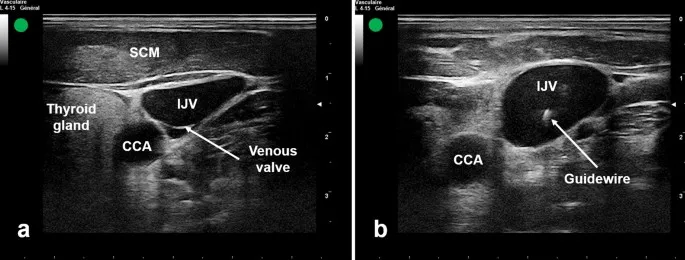

- Sites: Internal jugular (IJ), subclavian, and femoral veins. IJ is often preferred due to lower pneumothorax risk than subclavian.

- Internal Jugular (IJ): Preferred site; lower pneumothorax risk with ultrasound guidance.